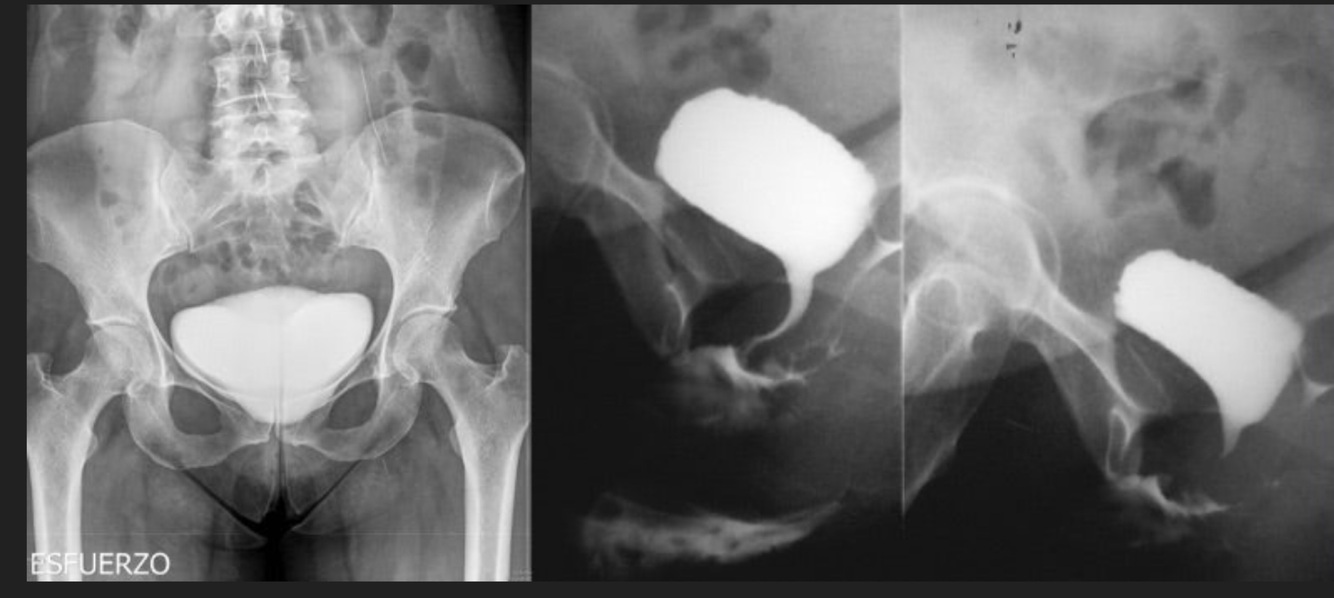

9

Q

Mujer, al efectuar esfuerzo (toser, hacer ejercicio, cargar algo pesado) presenta fuga de orina

A

Vejiga de esfuerzo, incontinencia urinaria, cistocele